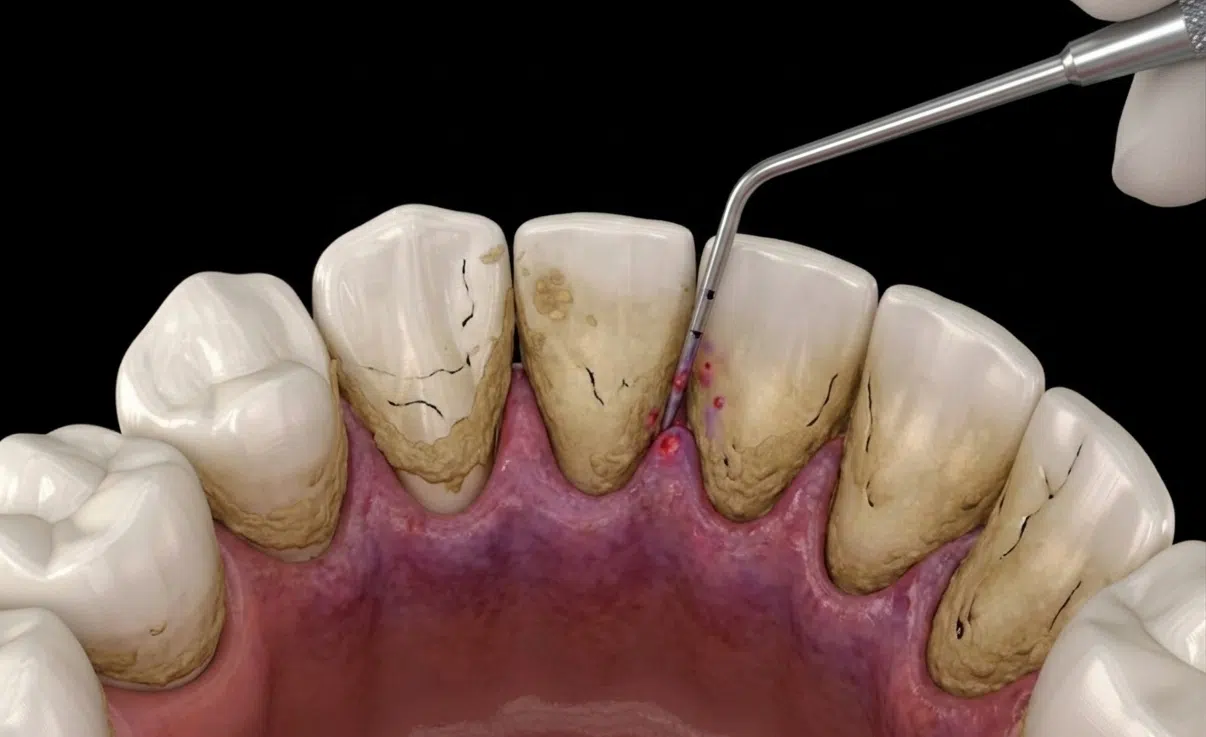

Understanding the Plaque Factor

Precision Targeting: A tiny laser fiber, about the width of three human hairs, is inserted between the gum and tooth.

Preservation: Only infected tissue is removed, leaving healthy gums intact.

Rapid Recovery: Patients enjoy significantly faster healing times and more predictable, long-term results compared to traditional surgery.